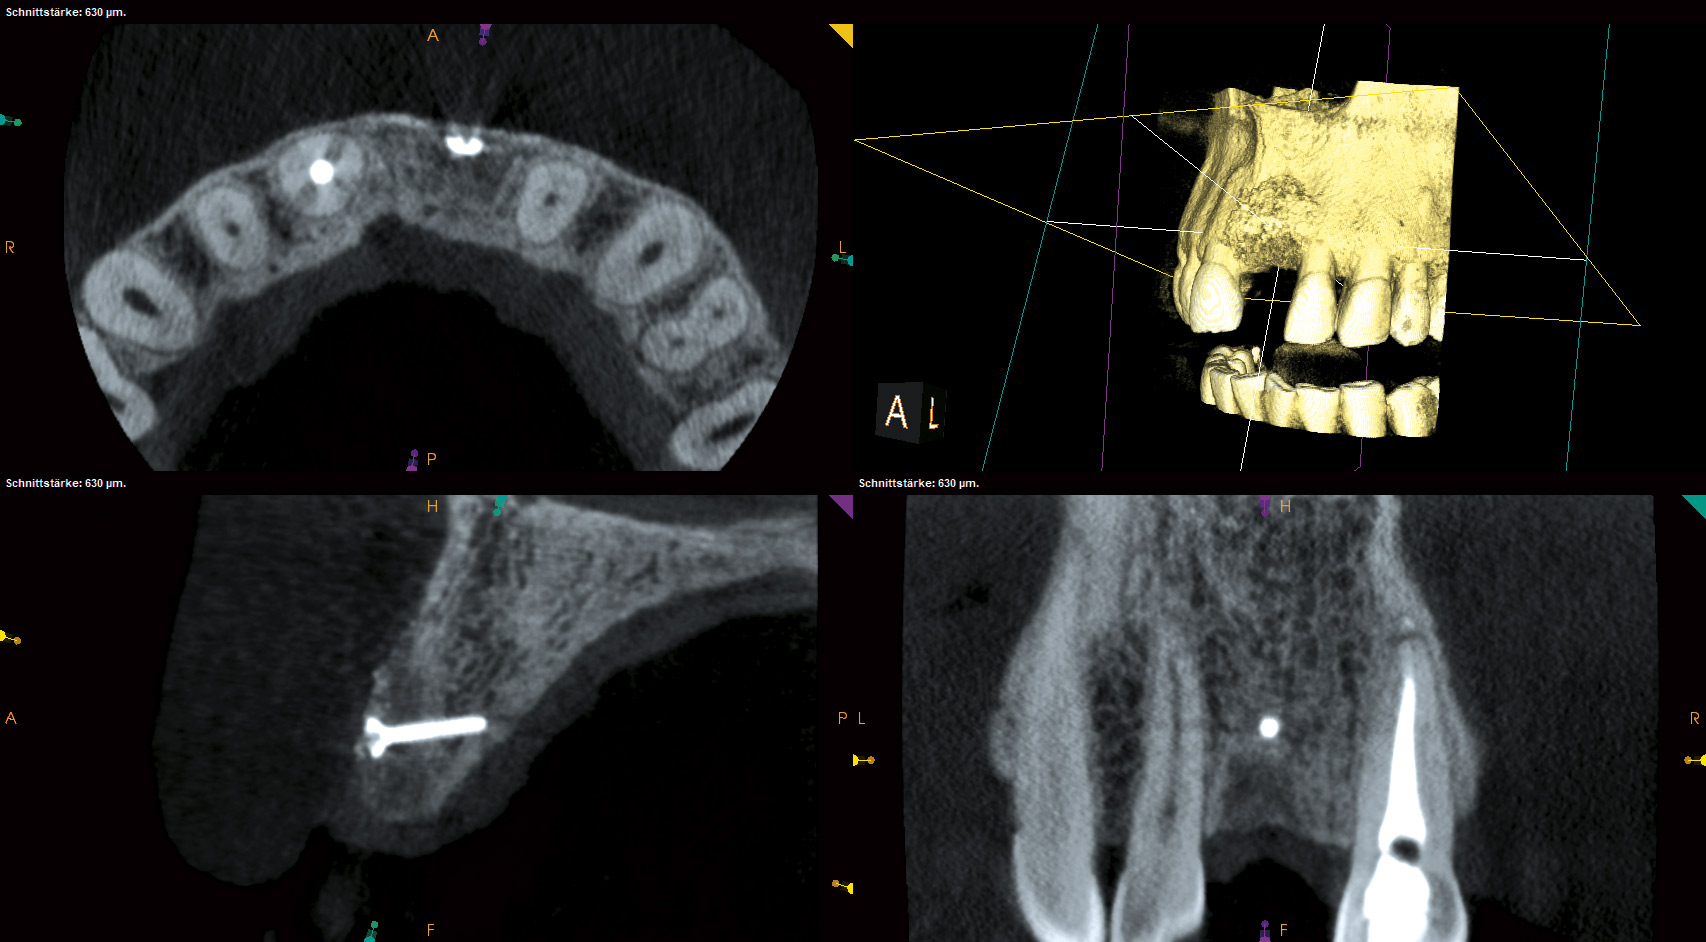

01/18 - Initial CBCT scan - Fracture of left maxillary incisor and loss of buccal wall

Block augmentation with maxgraft® and cerabone® – PD Dr. Dr. F. Kloss